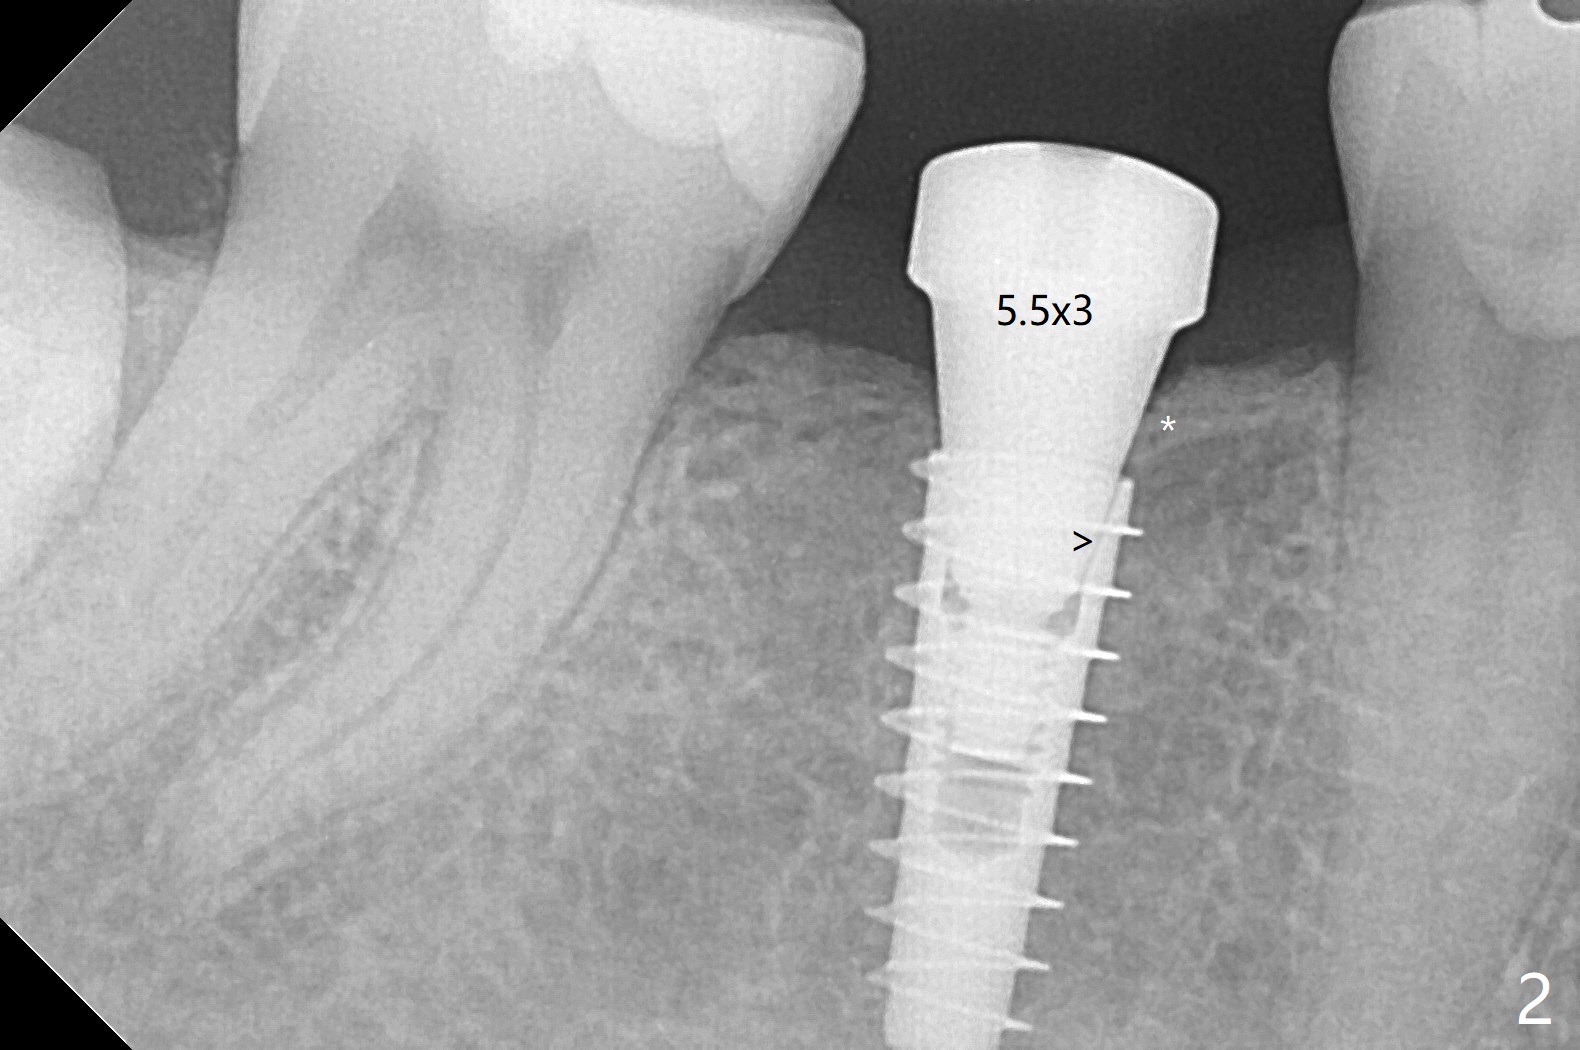

54岁男右下6缺失至少20年,牙槽嵴萎缩,使用导板顺利快速(五分钟)无痛植入4.5x11毫米植体(图一)。使用5.5毫米profile钻头后,放置6x2毫米愈合基台,后者明显没有就位(图二:箭头)。换一个基台,就位好些(图二)。再次使用同一个profile钻头后,可能去除一些近中皮质骨(图二:*),同一个基台完全就位(图三,四(红色虚线:下牙槽神经管上缘)),在愈合过程,基台不太可能脱落了。图一,二使用小sensor,而图三,四:大sensor。尽管使用小钻头(3.5毫米),扭力约20Ncm。